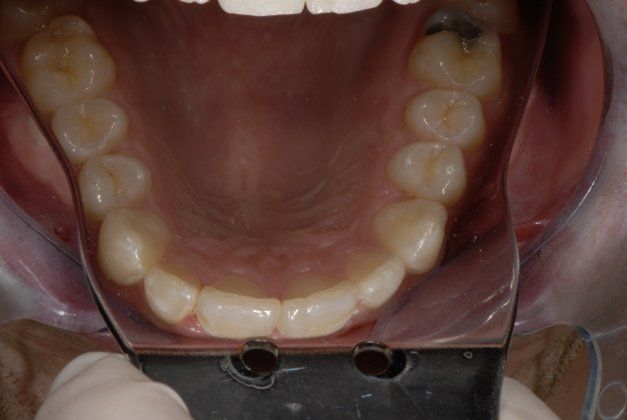

Invisalign Before & After

If you have healthy teeth and gums and wish to correct mild to moderate misalignment, you are likely a good candidate for orthodontics with aligners. Invisalign can correct:

- Crooked teeth

- Gaps between teeth

- Protruding upper teeth

- Overlapping or crowded teeth

- Overbites, underbites, crossbites, or open bites